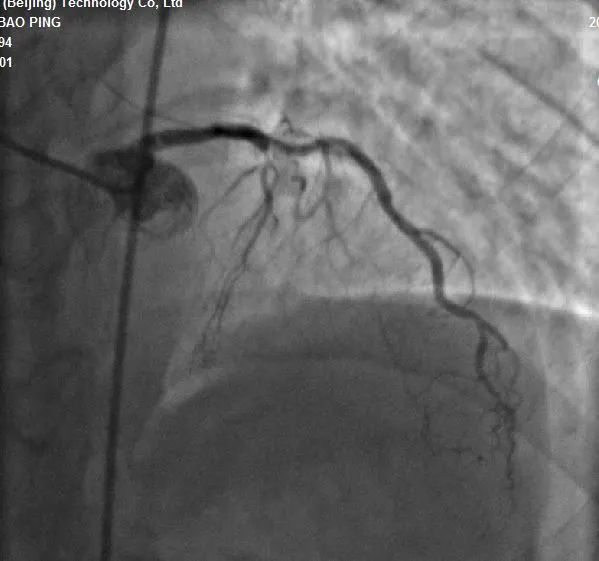

术前造影结果

患者前降支动脉(LAD)近段为完全性闭塞病变,可见自右冠状动脉后降支(PD)经间隔支向前降支提供侧枝循环,考虑该处病变为慢性完全闭塞性病变(CTO)。经过北京安贞医院孙涛主任与冯翠萍主任心血管内科介入团队的充分讨论,结合患者病史、症状及体征,考虑介入策略选择逆向处理。双侧通路:右冠:右股动脉;左冠:左侧桡动脉。